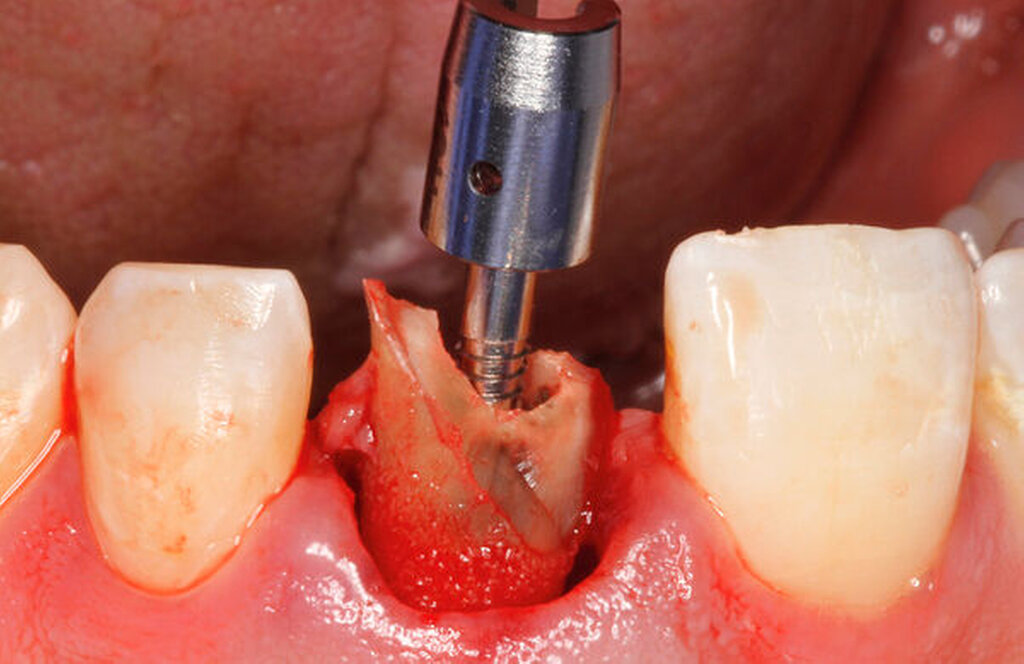

Bei der chirurgischen Extrusion (Synonym: intra-alveoläre Transplantation) wird der betroffene Zahn oder die betroffene Wurzel chirurgisch weiter koronal positioniert, um die Anfertigung einer adäquaten Restauration zu ermöglichen. Ihr biologisches Prinzip ist eingehend beschrieben worden mit guten Erfolgen im Tiermodell [Oikarinen et al., 1996] und in der klinischen Anwendung [Caliskan et al., 1999; Das und Muthu, 1999; Krug et al., 2018]. Die Technik wird bisher kaum in der zahnärztlichen Praxis angewendet, vermutlich aufgrund der begrenzten Vorhersagbarkeit, einen schwer kompromittierten Zahn oder eine Zahnwurzel erhalten zu können, wenn auf konventionelle Art und Weise extrahiert wird. Zum einen besteht das Risiko, durch die Extraktion eine Zahnfraktur zu verursachen, die den Zahnverlust zur Folge hat. Zum anderen führt die Anwendung von Luxatoren, Elevatoren oder Periotomen zu einer Aufdehnung der Alveole sowie zu Schäden am parodontalen Gewebe und gegebenenfalls an der Zahnwurzel selbst. Die Herausforderungen bei einer Zahnmobilisation für eine chirurgische Extrusion bestehen darin, weiteren Schaden an den Strukturen von Zahnhartsubstanz, Knochen und parodontalem Ligament zu vermeiden. Gelingt dies, können deren Hauptrisiken wie Zahnfraktur und progressive Wurzelresorption minimiert werden [Elkhadem et al., 2014].

Zur chirurgischen Extrusion werden meist Extraktionszangen verwendet. Die Zahnwurzel wird dabei idealerweise mit einer diamantierten Zange gefasst und durch Rotation vorsichtig entfernt. Insbesondere bei Zähnen mit runden Wurzeln ist diese Technik auch weitgehend schonend für das parodontale Ligament. Der forcierte Einsatz von Hebeln oder Luxationsbewegungen ist zu vermeiden, da diese zu parodontalen Schäden auf der Wurzeloberfläche führen können und somit die parodontale Heilung nach Replantation gefährden.

Eine weitere Möglichkeit, tief zerstörte Zähne möglichst schonend chirurgisch zu extrudieren, basiert auf axialen Zugsystemen (Abbildungen 2 bis 4). Diese erscheinen vorteilhaft bei sehr schwierigen Fällen, zum Beispiel bei Zähnen mit fehlendem Ansatzpunkt für die Zange sowie bei langen oder sehr ovalen Wurzeln. Axiale Zugsysteme ermöglichen die Übertragung von Zugkräften auf die Zahnwurzel, ohne die Alveole unnötig zu dehnen. Dazu wird eine spezielle Schraube in den Wurzelkanal eingebracht und das Gewinde der Schraube für eine ausreichende Friktion fingerfest eingedreht. An diese Schraube wird ein gerätespezifisches Zugsystem angelegt. Durch rein axial wirkende Zugkräfte werden traumatische Effekte auf Knochen und Wurzeloberfläche während der Zahnmobilisation minimiert. Gegebenenfalls können feine Luxatoren vorsichtig unterstützend eingesetzt werden. Im Tiermodell wurde an extrahierten und wieder replantierten Zähnen mit ovalem Querschnitt gezeigt, dass der Verlust von Zementoblasten auf der Wurzeloberfläche geringer ist, wenn ein axiales Zugsystem anstatt einer Extraktionszange verwendet wird.

Die wesentliche technische Komplikation stellt das unverhältnismäßige Erweitern des Wurzelkanals für die Retention des Zughilfsmittels – zum Beispiel der Benex-Schraube – dar. Der Behandler sollte hier unter besonderer Vorsicht den bereits instrumentierten und präparierten (vorgegebenen) Wurzelkanal als Bohr- und Zugpfad für die Extrusion nutzen. Auf die Schonung der gesunden Zahnhartsubstanz muss geachtet werden. Die Bohrachse für die Ausrichtung der Zugschraube muss mit dem koronal gelegenen Hauptpfad des Wurzelkanals übereinstimmen. Zudem ist für das Erzielen einer ausreichenden Retention der Schraube ein gewisses Maß an Feingefühl und Taktilität vom Behandler erforderlich. Eine neue Schraube erfüllt die Vorbedingung eines schneidfreudigen Gewindes und damit eines guten Halts im Zahn am besten.